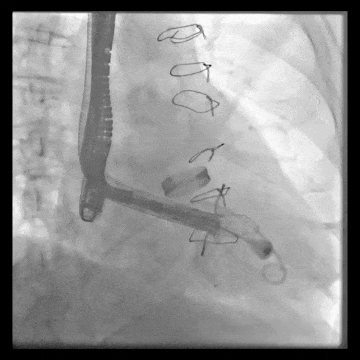

術后DSA、超聲顯示人工瓣膜穩定性良好,瓣葉啟閉正常,無瓣周漏

術后DSA